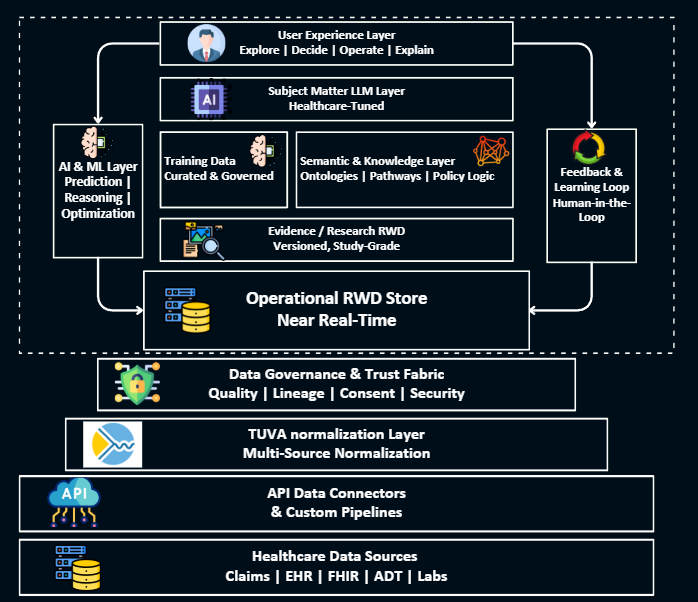

Commercial Data Platform Strategy

We design and build commercial data platforms that integrate IQVIA, Symphony, claims, EHR, and internal data into a single, governed commercial intelligence layer — enabling faster decisions across brand, market access, and field teams.

- Commercial data architecture and platform design

- IQVIA, Symphony, SHA, MMIT data integration

- Commercial dashboards and self-service analytics

- Executive-level brand performance reporting

- Data governance and master data management